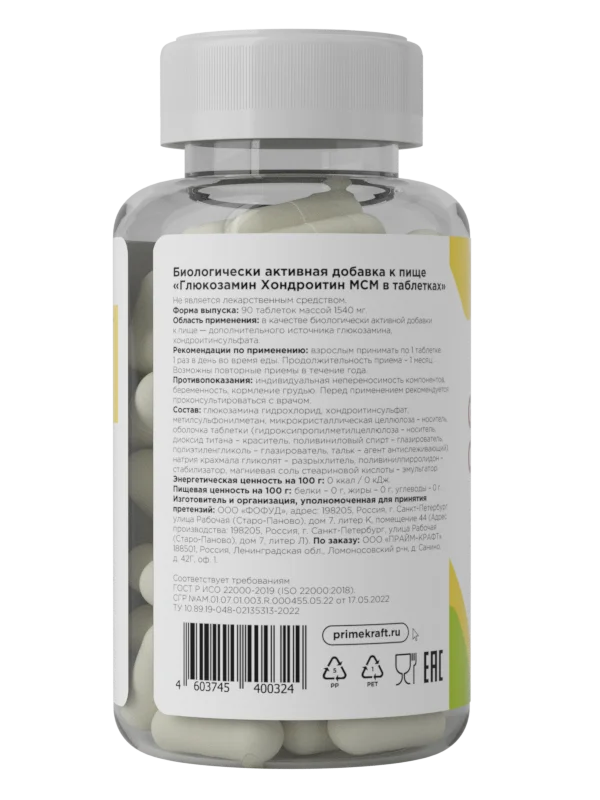

Как видите, выбирать между ними – так себе затея. Исходя из свойств каждой добавки, можно с уверенностью сказать, что лучшие препараты для суставов и связок – это хондропротекторы нового поколения, многокомпонентные. Например, в хондропротекторе от Prime Kraft дополнительно к хондроитину и глюкозамину содержится MСM – метилсульфонилметан, противовоспалительное средство для суставов, которое ускоряет поступление питательных веществ в клеточные мембраны и снижает болевые ощущения в связках и суставах.

Хондропротектор пьют курсами, 1-3 месяца 2-3 раза в год , в зависимости от состояния ваших суставов. По 1 капсуле 1 раз в день во время еды, в восстановительный период после травм и повреждений - 2 раза в день.